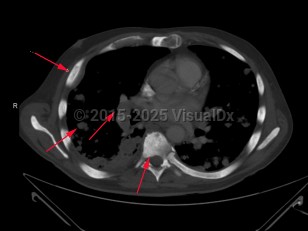

Metastatic prostate carcinoma

Prostate gland carcinoma that has disseminated. Metastatic prostate carcinoma is seen less frequently due to prostate-specific antigen screening, which enables early diagnosis of prostate cancer while it is still localized. Malignant cells can appear throughout the body as cancer advances, with the bones and lymph nodes more commonly affected.

In patients with bone metastasis, the axial skeleton is often involved. Common findings include bone pain, pathologic fracture, and spinal cord compression may be observed. Patients with lymph node involvement will present with regional or cervical lymphadenopathy. Masses may also be observed, especially in the neck. The skin, liver, and penis are also reported areas of involvement.